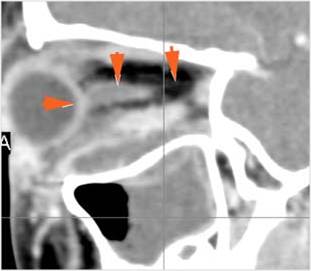

Orbits

The extraconal orbital fat is abnormal. [Yes/No]

There is a subperiosteal abscess or edema along the medial wall, roof or floor of the orbit. [Yes/No]

The extraocular muscles are swollen or otherwise abnormal. [Yes/No]

There is bone erosion along the walls of the orbit. [Yes/No]

The intraconal orbital fat is infiltrated. [Yes/No]

The orbital apex and the superior and inferior orbital fissures are infiltrated. [Yes/No]

The superior and/or inferior ophthalmic veins are dilated or thrombosed. [Yes/No]